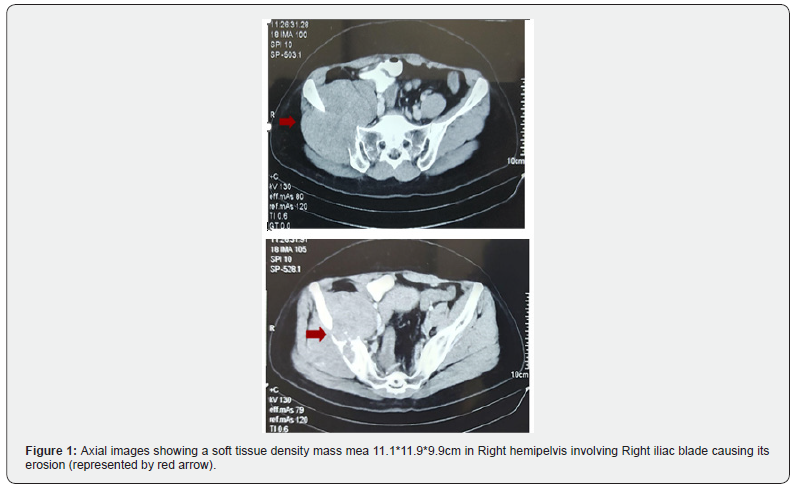

We present the case of 51 yrs old female k/c HTN presented in Jan 2023 with pain in Rt leg with a palpable lesion near Rt gluteal region. She had significant past history of Left sided ooAbstract phorectomy in 2001, histopathology of which consistent with granulosa cell tumor of ovary after which she was kept on surveillance. On examination she was a lady of average built, walking with support and unable to bear weight on Rt side of leg with tender lesion over Right buttock area. She got a CT scan done on 5th Jan,23 that showed soft tissue density mass in Right hemipelvis mea 11.1*11.9*9.9cm, there were also soft tissue density nodules in bilateral lung fields likely metastatic deposits Figure 1. PET/CT scan was also done on 15th feb, 23 showed neoplastic lesion in Rt iliac bone with infiltration into adjacent muscles and metastatic deposits in lungs with suspicious solitary Rt external iliac vessel lymph node Figures 1-3.

Bone metastasis from ovarian GCT represents an unusual pattern of spread, likely reflecting hematogenous dissemination rather than the more common local or lymphatic routes. Reported cases include metastases to vertebrae, clavicle, humerus, and other skeletal sites, often presenting as isolated lytic lesions causing pain or pathological fractures [4,5,8]. In our case patients presented with a soft tissue density mass in the right hemipelvis and bilateral lung fields, suggestive of metastatic deposits causing her local pain and limping gait because of local destruction of pelvic bone and uptill now as per literature search is reported to be the second case of granulosa cell tumor involving the pelvis [9].